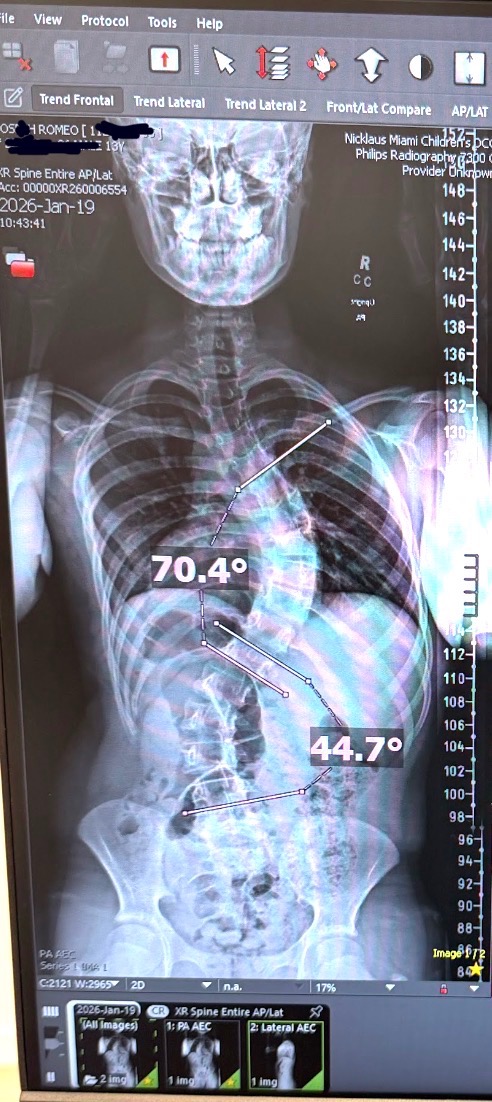

Romeo is a brave 14-year-old preparing for a major scoliosis surgery on April 10th 2026. This is a critical step toward improving his health and preventing further complications.